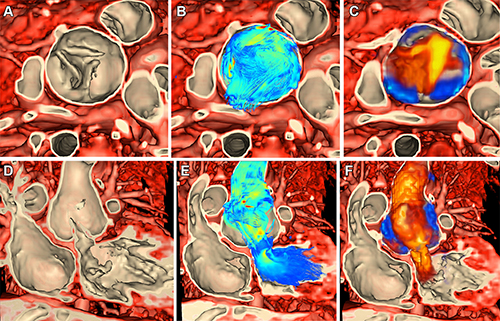

Figure 2. Volume rendering of ferumoxytol-enhanced inversion-recovery fast low-angle shot imaging from cardiac MRI in a 6-year-old female patient with a right ventricle to aorta and malalignment ventricular septal defect (VSD) (patient 2) to inform planning of biventricular repair. (A) Sagittal and (B) coronal views demonstrate VSD (green arrow). (C) Volume rendering of cardiac MRI. (D) Volume rendering with baffle placement using SlicerHeart.

Figure 3. Volume rendering of ferumoxytol-enhanced cardiac MR images using image-based navigation (ie, iNav) to inform closure of multiple ventricular septal defects (VSDs) in a 3-year-old female patient (patient 3). (A) Multiplane reconstruction of volume demonstrates muscular VSD (green arrow). (B) Volume rendering of the myocardium from right ventricular view. (C) Volume rendering of the myocardium from left ventricular view. (D) Simulated VSD closure (blue) and device placement (green) within volume-rendered images.